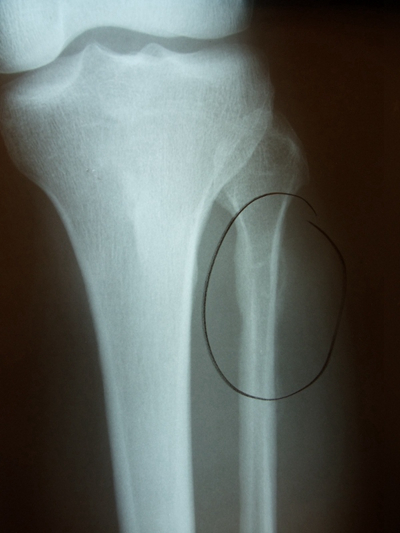

骨折圖片

骨裂